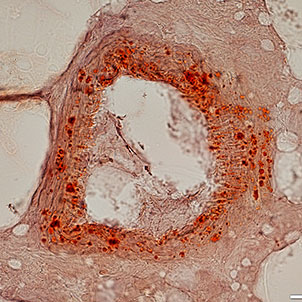

- Confirmation of the nature of differentiated cells by ICC method

- Investigation of cell placement on tissue scaffold